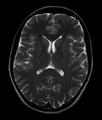

- T2: CSF is light, but fat (and thus white matter) is darker than with T1. T2 is useful for visualizing pathology.[14]

Normal axial T2-weighted MR image of the brain.